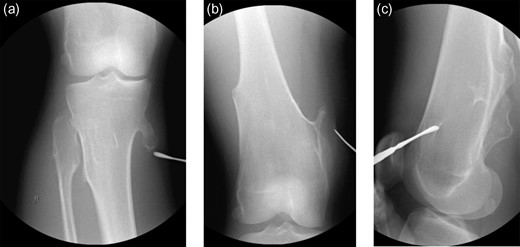

The procedure began with examination under anesthesia—the right leg could be forcefully extended but resulted in significant tension about the posteromedial soft tissues of the leg. The limb was circumferentially prepped and draped in the standard orthopedic fashion without the use of a tourniquet. The osteochondromas were localized (Fig. 2a–c) and exploration revealed a bursa superficial to the osteochondroma. The gracilis tendon was in its appropriate anatomic position cranial to the pedunculated osteochondroma. The semitendinosus tendon was incarcerated inferior to the osteochondroma (Fig. 3a), creating the locked knee effect. The hooked tendon was protected, and the 3 cm osteochondroma (Fig. 3b) was removed with an oscillating saw, freeing the entrapped tendon and restoring normal movement of her knee. Radiographic imaging (Fig. 4a and b) confirmed satisfactory removal of the lesions, and the wounds were closed. At the 3-month follow-up, the patient had returned to all desired activities with no recurrent medial knee pain or locking.

(a–c) Initial intraoperative radiographic images obtained to locate the lesions.